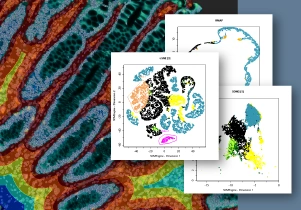

StrataQuest 8 also supports manifold learning techniques, also known as dimensionality reduction: t-SNE, UMAP, and SONG (A). Nonparametric t-SNE (t-distributed Stochastic Neighbor Embedding) and UMAP (Uniform Manifold Approximation and Projection) are widely used for analysis of large, high-dimensional datasets, commonly derived from single-cell RNAseq or multi/hyperplex staining. SONG algorithm (Self Organizing Nebulous Growths) was published in 2020 by Senanayake and colleagues and represents a parametric nonlinear dimensionality reduction technique that supports incremental data visualization, i.e., addition of new data while preserving the structure of the existing visualization. Each technique may have certain advantages or disadvantages for some applications. Depending on the user’s specific needs, StrataQuest offers to visualize image analysis data using all of the mentioned methods.

Within these diagrams (Figure 8) it is possible to gate the cell populations of interest and trace back to their spatial distribution. The example (B) shows two gated populations on a t-SNE plot and gated cells on the tissue sample in red contour. This way, a population of interest can be immediately selected and traced back to its location.

Figure 8. Phenotype extraction.